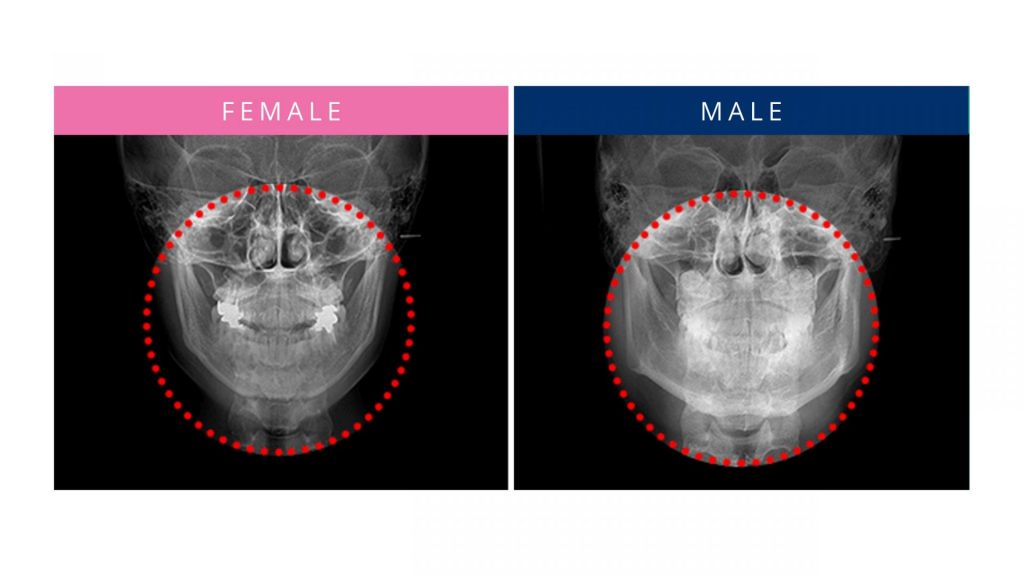

Differences in The Facial Bone Structure of Men and Women

With facial contouring surgery, it is important to change the facial shape into a new and balanced contour by performing surgery that is customised to the existing bone structure of your face. It’s not just about cutting and reducing the size of the protruding bone, but also about recrafting the surgical area in consideration of all surrounding features as well as aligning the features with the wishes of the patient. Therefore, it is very important to make detailed plans about the result you want with a specialist surgeon through in-depth consultation. This includes considering how each patient chooses to express their gender identity, because each person will have a different goal along the spectrum of masculinisation and feminisation. It is recommended that patients do good research about what kind of face shape they want and collect the opinions of experts to make their decision.

As another thing to consider, and speaking broadly about gender, many male patients wish for a slight trimming of the protruding bones such as cheekbones and square jaws, creating a face shape that can enhance masculinity by sharpening the jawline. Whereas many female patients want to create a small and soft face shape. In particular, there are many cases where v-line surgery is the key to achieving these particular shapes.

The design of the facial contour varies according to gender expression, so the purpose and result should, of course, be different between more masculine leaning patients and more feminine leaning patients. For masculinisation, the focus should be on the lines that can emphasise the masculine traits of the face, such as the jawbones, cheekbones and overall facial projection. And for feminization, it is important to plan and conduct the surgery so that the patient maintains the width of their chin properly in order to avoid a “sharp” or “pointed” look. Biological gender also plays a role, as male and female faces typically have different structures. So a patient desiring to go in the other direction, such as a transgender patient, needs even more specialist treatment. Cheekbone reduction and v-line surgery in combination, can form a face shape that can properly suit anyone’s taste.